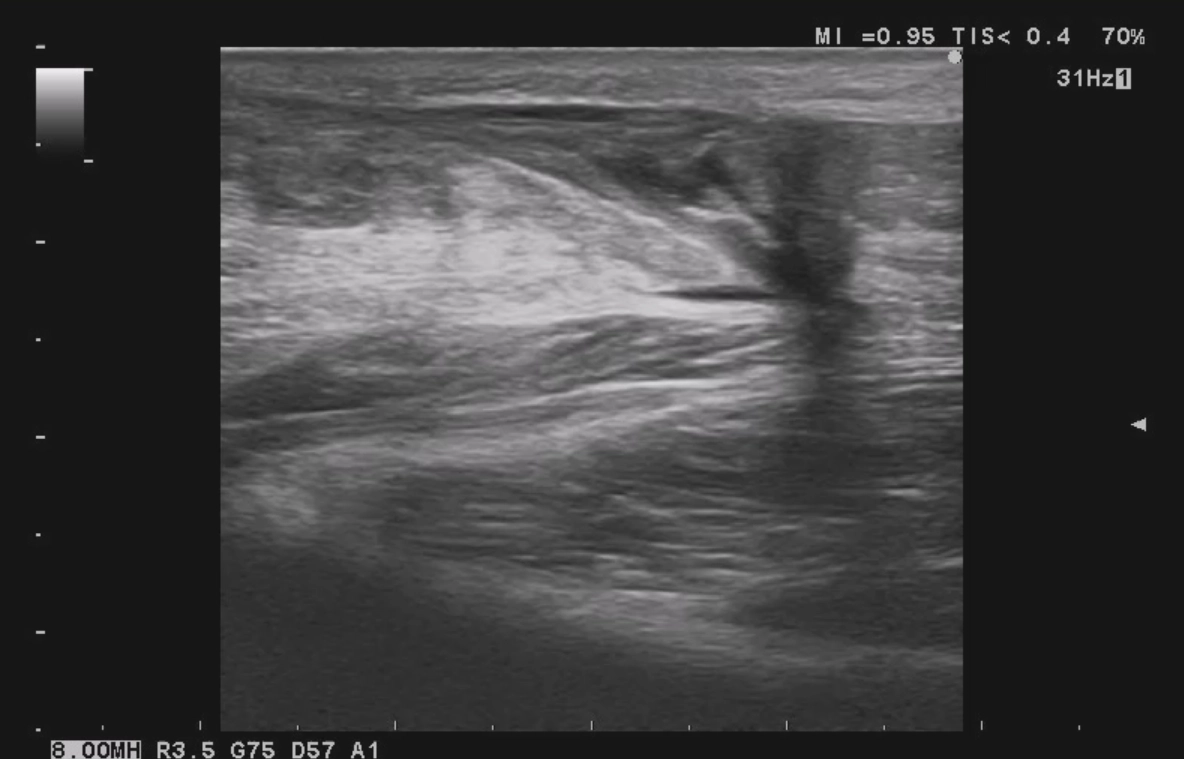

超音波で断裂部の確認 1日目

患部がどの程度断裂しているかを評価します。

完全断裂では、つま先を下げるように固定角度を強くします。

また、固定期間などの施術スケジュールも大まかに判断します。 -

その際ににアキレス腱の様子を確認します。

この段階で順調にアキレス腱がくっついているかを超音波検査で確認した後、足首に少し角度をつけて再びギプス固定を行います。 -

超音波観察にて患部を確認し、当院にて再固定。約5ヶ月後に可動域・筋力ともに日常生活に支障がなくなり施術終了となりました。